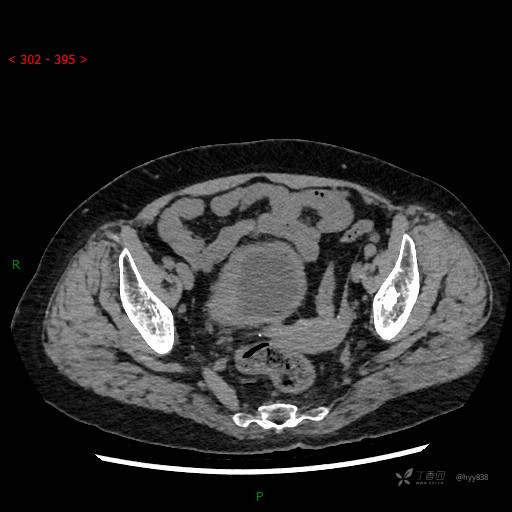

辅助检查:CT

膀胱CT平扫(2022.10.20)

增强(2022.11.1)